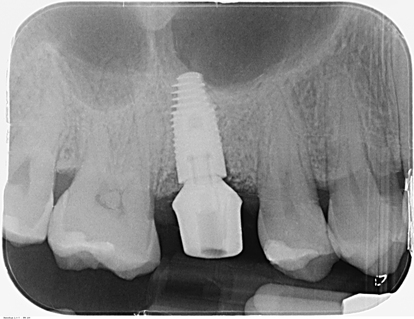

Advan e la sistematica One Internal, con la superficie OsseoGrip®, mette a disposizione del clinico una superficie ad alta capacità osteointegrativa con una connessione oramai standardizzata capace di semplificare le procedure protesiche. Tutto questo, ci ha permesso di arrivare ad un risultato impla-protesico soddisfacente, con una ricostruzione di tessuto mucoso interprossimale, che armonizza il nostro manufatto protesico con il tessuto circostante. Si è eseguito un controllo radiografico a tre anni (anche se il lasso di tempo non è completamente significativo) dove si è potuto notare un corretto mantenimento osseo e trofismo gengivale (Fig.16). La paziente infatti riesce a mantenere una buona igiene domiciliare senza grosse difficoltà.